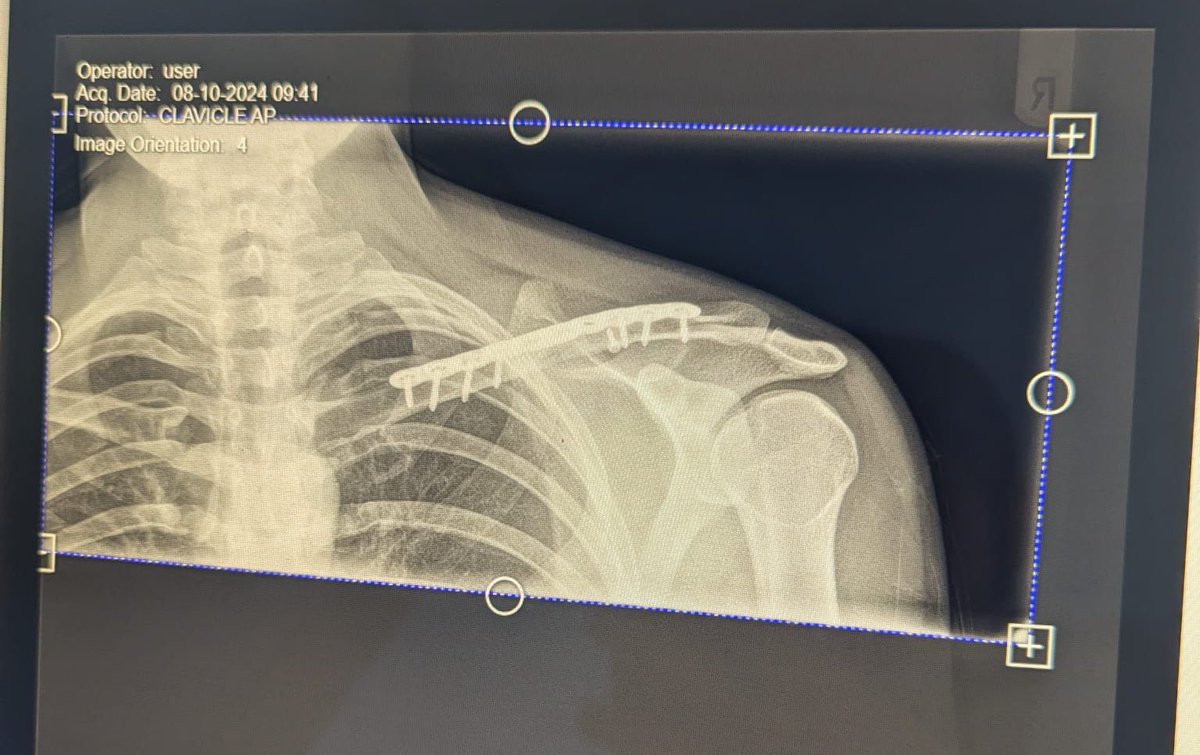

Our CDM the suffered a fracture of the collar bone result in it breaking into 4 piece has had surgery and now is on the road to recovery 🙌🏽 thank you for all the well wishes! Hopefully have you back in the pitch with us soon double plated up Andrew Steele

Our CDM the suffered a fracture of the collar bone result in it breaking into 4 piece has had surgery and now is on the road to recovery 🙌🏽 thank you for all the well wishes! Hopefully have you back in the pitch with us soon double plated up <a href="/A_steele_94/">Andrew Steele</a>